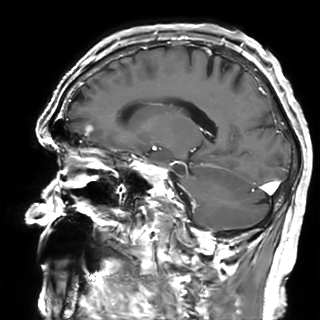

Figure 6: Qualitative evaluation on the RLS dataset. The top row depicts a 33%percent3333\%33 % low-dose sample, where the yellow zoom highlights the lesion. The bottom row shows a case with a 10%percent1010\%10 % real low-dose image and the lesion is marked by the yellow circles.

Refer to captionRefer to caption𝐱PCsubscript𝐱PC\mathbf{x}_{\mathrm{PC}}bold_x start_POSTSUBSCRIPT roman_PC end_POSTSUBSCRIPTRefer to captionRefer to caption𝐱LDsubscript𝐱LD\mathbf{x}_{\mathrm{LD}}bold_x start_POSTSUBSCRIPT roman_LD end_POSTSUBSCRIPTRefer to captionRefer to caption𝐱SDsubscript𝐱SD\mathbf{x}_{\mathrm{SD}}bold_x start_POSTSUBSCRIPT roman_SD end_POSTSUBSCRIPTRefer to captionRefer to captionAm-3D [14]Refer to captionRefer to captionPa-2.5D [8]Refer to captionRefer to caption𝐱~SDsubscript~𝐱SD\tilde{\mathbf{x}}_{\mathrm{SD}}over~ start_ARG bold_x end_ARG start_POSTSUBSCRIPT roman_SD end_POSTSUBSCRIPT (ours)ptPhilips Achieva 3TGadobutrol dLD=0.10subscript𝑑LD0.10d_{\mathrm{LD}}=0.10italic_d start_POSTSUBSCRIPT roman_LD end_POSTSUBSCRIPT = 0.10ptPhilips Ingenia 1.5TGadoterate dLD=0.33subscript𝑑LD0.33d_{\mathrm{LD}}=0.33italic_d start_POSTSUBSCRIPT roman_LD end_POSTSUBSCRIPT = 0.33Refer to captionRefer to caption𝐱PCsubscript𝐱PC\mathbf{x}_{\mathrm{PC}}bold_x start_POSTSUBSCRIPT roman_PC end_POSTSUBSCRIPTRefer to captionRefer to caption𝐱LDsubscript𝐱LD\mathbf{x}_{\mathrm{LD}}bold_x start_POSTSUBSCRIPT roman_LD end_POSTSUBSCRIPTRefer to captionRefer to caption𝐱SDsubscript𝐱SD\mathbf{x}_{\mathrm{SD}}bold_x start_POSTSUBSCRIPT roman_SD end_POSTSUBSCRIPTRefer to captionRefer to captionAm-3D [14]Refer to captionRefer to captionPa-2.5D [8]Refer to captionRefer to caption𝐱~SDsubscript~𝐱SD\tilde{\mathbf{x}}_{\mathrm{SD}}over~ start_ARG bold_x end_ARG start_POSTSUBSCRIPT roman_SD end_POSTSUBSCRIPT (ours)ptPhilips Achieva 3TGadobutrol dLD=0.10subscript𝑑LD0.10d_{\mathrm{LD}}=0.10italic_d start_POSTSUBSCRIPT roman_LD end_POSTSUBSCRIPT = 0.10ptPhilips Ingenia 1.5TGadoterate dLD=0.33subscript𝑑LD0.33d_{\mathrm{LD}}=0.33italic_d start_POSTSUBSCRIPT roman_LD end_POSTSUBSCRIPT = 0.33Refer to captionRefer to caption𝐱PCsubscript𝐱PC\mathbf{x}_{\mathrm{PC}}bold_x start_POSTSUBSCRIPT roman_PC end_POSTSUBSCRIPTRefer to captionRefer to caption𝐱LDsubscript𝐱LD\mathbf{x}_{\mathrm{LD}}bold_x start_POSTSUBSCRIPT roman_LD end_POSTSUBSCRIPTRefer to captionRefer to caption𝐱SDsubscript𝐱SD\mathbf{x}_{\mathrm{SD}}bold_x start_POSTSUBSCRIPT roman_SD end_POSTSUBSCRIPTRefer to captionRefer to captionAm-3D [14]Refer to captionRefer to captionPa-2.5D [8]Refer to captionRefer to caption𝐱~SDsubscript~𝐱SD\tilde{\mathbf{x}}_{\mathrm{SD}}over~ start_ARG bold_x end_ARG start_POSTSUBSCRIPT roman_SD end_POSTSUBSCRIPT (ours)ptPhilips Achieva 3TGadobutrol dLD=0.10subscript𝑑LD0.10d_{\mathrm{LD}}=0.10italic_d start_POSTSUBSCRIPT roman_LD end_POSTSUBSCRIPT = 0.10ptPhilips Ingenia 1.5TGadoterate dLD=0.33subscript𝑑LD0.33d_{\mathrm{LD}}=0.33italic_d start_POSTSUBSCRIPT roman_LD end_POSTSUBSCRIPT = 0.33Refer to captionRefer to caption𝐱PCsubscript𝐱PC\mathbf{x}_{\mathrm{PC}}bold_x start_POSTSUBSCRIPT roman_PC end_POSTSUBSCRIPTRefer to captionRefer to caption𝐱LDsubscript𝐱LD\mathbf{x}_{\mathrm{LD}}bold_x start_POSTSUBSCRIPT roman_LD end_POSTSUBSCRIPTRefer to captionRefer to caption𝐱SDsubscript𝐱SD\mathbf{x}_{\mathrm{SD}}bold_x start_POSTSUBSCRIPT roman_SD end_POSTSUBSCRIPTRefer to captionRefer to captionAm-3D [14]Refer to captionRefer to captionPa-2.5D [8]Refer to captionRefer to caption𝐱~SDsubscript~𝐱SD\tilde{\mathbf{x}}_{\mathrm{SD}}over~ start_ARG bold_x end_ARG start_POSTSUBSCRIPT roman_SD end_POSTSUBSCRIPT (ours)ptPhilips Achieva 3TGadobutrol dLD=0.10subscript𝑑LD0.10d_{\mathrm{LD}}=0.10italic_d start_POSTSUBSCRIPT roman_LD end_POSTSUBSCRIPT = 0.10ptPhilips Ingenia 1.5TGadoterate dLD=0.33subscript𝑑LD0.33d_{\mathrm{LD}}=0.33italic_d start_POSTSUBSCRIPT roman_LD end_POSTSUBSCRIPT = 0.33Refer to captionRefer to caption𝐱PCsubscript𝐱PC\mathbf{x}_{\mathrm{PC}}bold_x start_POSTSUBSCRIPT roman_PC end_POSTSUBSCRIPTRefer to captionRefer to caption𝐱LDsubscript𝐱LD\mathbf{x}_{\mathrm{LD}}bold_x start_POSTSUBSCRIPT roman_LD end_POSTSUBSCRIPTRefer to captionRefer to caption𝐱SDsubscript𝐱SD\mathbf{x}_{\mathrm{SD}}bold_x start_POSTSUBSCRIPT roman_SD end_POSTSUBSCRIPTRefer to captionRefer to captionAm-3D [14]Refer to captionRefer to captionPa-2.5D [8]Refer to captionRefer to caption𝐱~SDsubscript~𝐱SD\tilde{\mathbf{x}}_{\mathrm{SD}}over~ start_ARG bold_x end_ARG start_POSTSUBSCRIPT roman_SD end_POSTSUBSCRIPT (ours)ptPhilips Achieva 3TGadobutrol dLD=0.10subscript𝑑LD0.10d_{\mathrm{LD}}=0.10italic_d start_POSTSUBSCRIPT roman_LD end_POSTSUBSCRIPT = 0.10ptPhilips Ingenia 1.5TGadoterate dLD=0.33subscript𝑑LD0.33d_{\mathrm{LD}}=0.33italic_d start_POSTSUBSCRIPT roman_LD end_POSTSUBSCRIPT = 0.33Refer to captionRefer to caption𝐱PCsubscript𝐱PC\mathbf{x}_{\mathrm{PC}}bold_x start_POSTSUBSCRIPT roman_PC end_POSTSUBSCRIPTRefer to captionRefer to caption𝐱LDsubscript𝐱LD\mathbf{x}_{\mathrm{LD}}bold_x start_POSTSUBSCRIPT roman_LD end_POSTSUBSCRIPTRefer to captionRefer to caption𝐱SDsubscript𝐱SD\mathbf{x}_{\mathrm{SD}}bold_x start_POSTSUBSCRIPT roman_SD end_POSTSUBSCRIPTRefer to captionRefer to captionAm-3D [14]Refer to captionRefer to captionPa-2.5D [8]Refer to captionRefer to caption𝐱~SDsubscript~𝐱SD\tilde{\mathbf{x}}_{\mathrm{SD}}over~ start_ARG bold_x end_ARG start_POSTSUBSCRIPT roman_SD end_POSTSUBSCRIPT (ours)ptPhilips Achieva 3TGadobutrol dLD=0.10subscript𝑑LD0.10d_{\mathrm{LD}}=0.10italic_d start_POSTSUBSCRIPT roman_LD end_POSTSUBSCRIPT = 0.10ptPhilips Ingenia 1.5TGadoterate dLD=0.33subscript𝑑LD0.33d_{\mathrm{LD}}=0.33italic_d start_POSTSUBSCRIPT roman_LD end_POSTSUBSCRIPT = 0.33Refer to captionRefer to caption𝐱PCsubscript𝐱PC\mathbf{x}_{\mathrm{PC}}bold_x start_POSTSUBSCRIPT roman_PC end_POSTSUBSCRIPTRefer to captionRefer to caption𝐱LDsubscript𝐱LD\mathbf{x}_{\mathrm{LD}}bold_x start_POSTSUBSCRIPT roman_LD end_POSTSUBSCRIPTRefer to captionRefer to caption𝐱SDsubscript𝐱SD\mathbf{x}_{\mathrm{SD}}bold_x start_POSTSUBSCRIPT roman_SD end_POSTSUBSCRIPTRefer to captionRefer to captionAm-3D [14]Refer to captionRefer to captionPa-2.5D [8]Refer to captionRefer to caption𝐱~SDsubscript~𝐱SD\tilde{\mathbf{x}}_{\mathrm{SD}}over~ start_ARG bold_x end_ARG start_POSTSUBSCRIPT roman_SD end_POSTSUBSCRIPT (ours)ptPhilips Achieva 3TGadobutrol dLD=0.10subscript𝑑LD0.10d_{\mathrm{LD}}=0.10italic_d start_POSTSUBSCRIPT roman_LD end_POSTSUBSCRIPT = 0.10ptPhilips Ingenia 1.5TGadoterate dLD=0.33subscript𝑑LD0.33d_{\mathrm{LD}}=0.33italic_d start_POSTSUBSCRIPT roman_LD end_POSTSUBSCRIPT = 0.33

A qualitative comparison of RLD test samples is shown in Figure 6. The required skull stripping and non-linear intensity normalization of Am-3D are readily apparent. Thus, a quantitative comparison to the target 𝐱SDsubscript𝐱SD\mathbf{x}_{\mathrm{SD}}bold_x start_POSTSUBSCRIPT roman_SD end_POSTSUBSCRIPT is not reasonable. Nevertheless, the CE signal strength in pathological regions (highlighted by the yellow circles) is well visible despite too smooth output images. The internal morphology and the border delineation also exhibit blurring. Pa-2.5D yields better image quality but the contrast strength in pathological regions is not well captured. In particular, the contrast signal overshoots for the 33%percent3333\%33 % low-dose scan in the first row and undershoots for the 10%percent1010\%10 % scan at the bottom, although the training dataset contains low-dose images at both dose levels. Our approach yields the highest image quality and predicts the contrast enhancement more accurately due to the focus on the enhancement signal and the conditional embeddings. As a result, our approach generates CE images preserving the image quality of the inputs by avoiding the synthesis of anatomical or noise patterns.